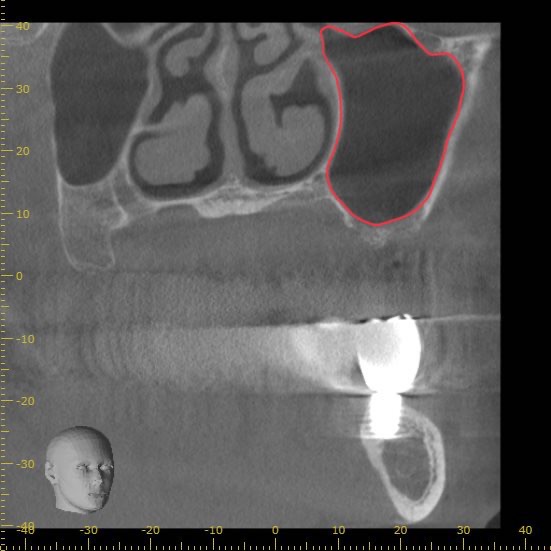

正面から見たCT画像です。

上顎の上方には副鼻腔(上顎洞)と呼ばれる、鼻とつながる空洞が存在します。

下の赤線で囲まれた部分です。

この部分にインプラントが飛び出してしまうと鼻に炎症を起こす可能性があるため、その下の骨の内部で留める必要があります。

今回の画像をみるとわかりますが、骨が極端に少ない状態です。

インプラントの半分以上に骨が足りない状態です。

現状の骨の状態でインプラントを行うこと自体が難しいと判断できます。